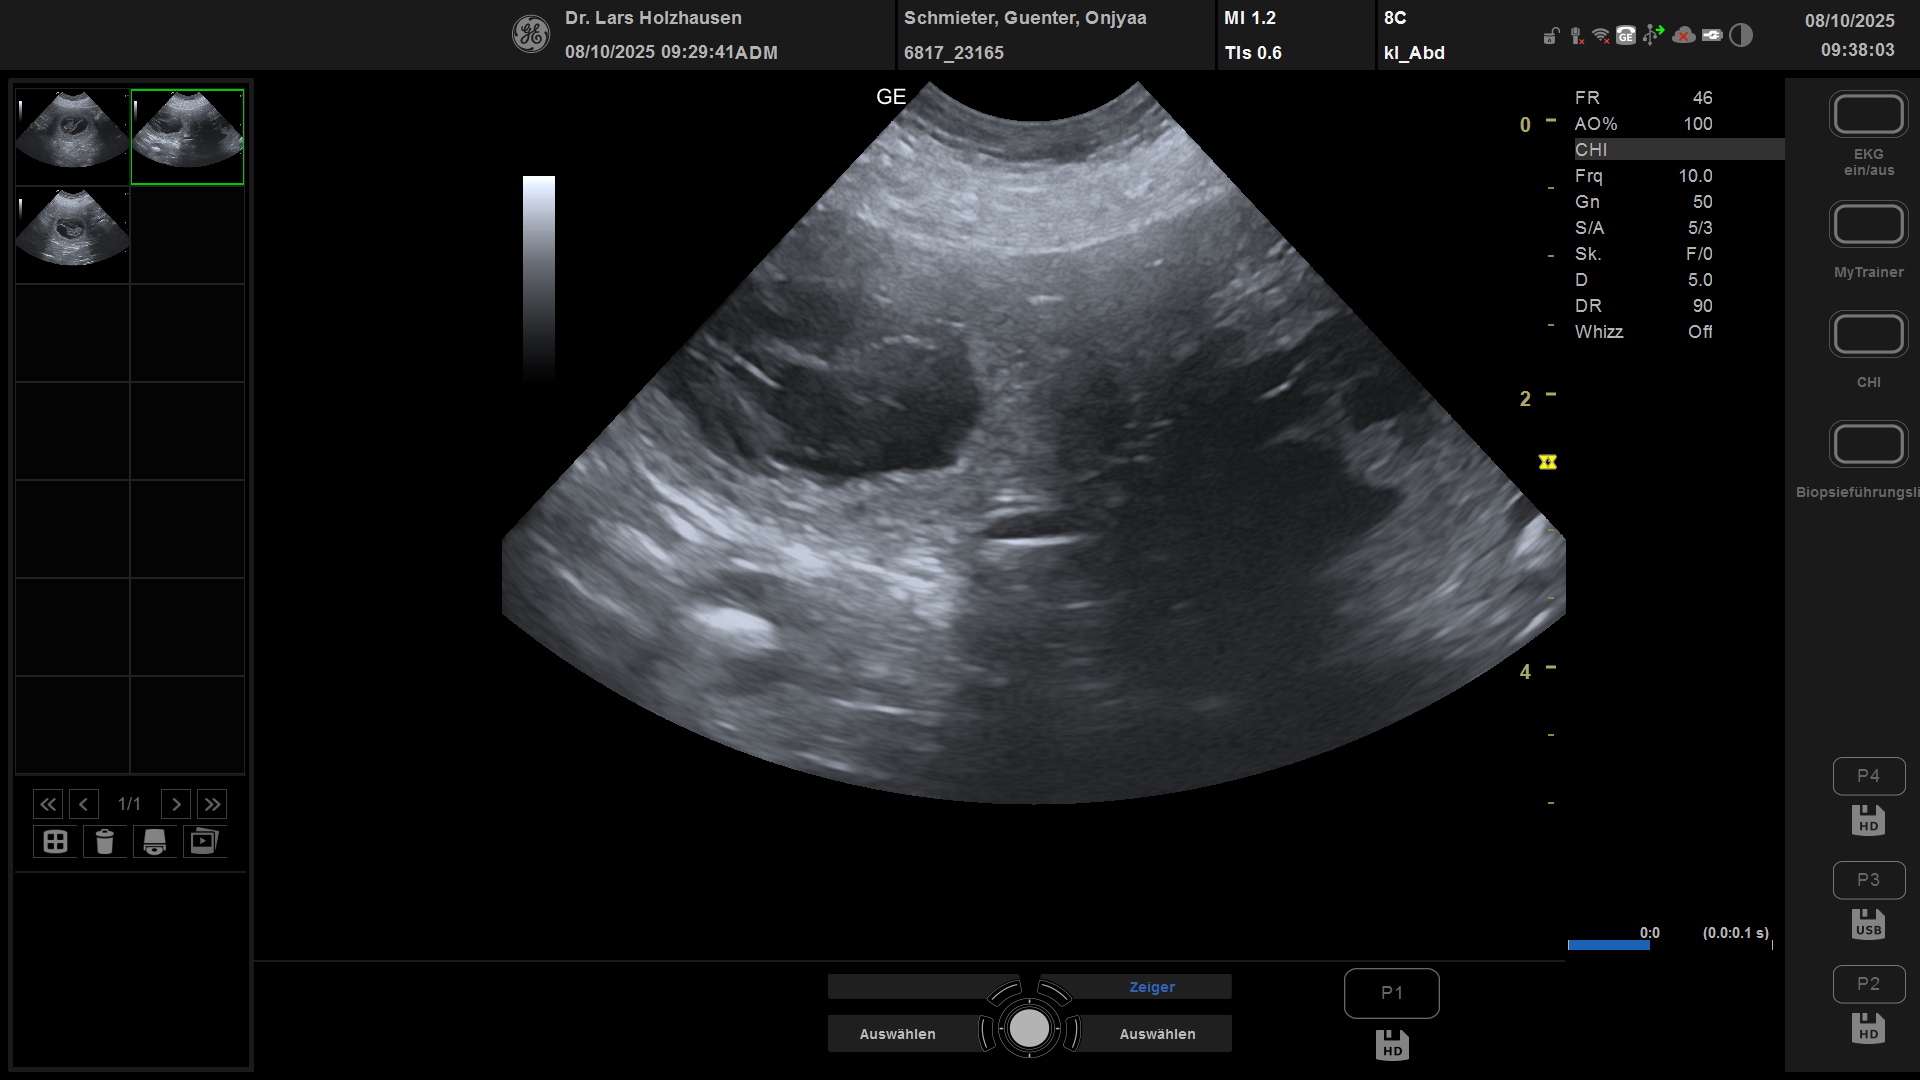

• 08.10.2025 Termin zum Ultraschall

zu: Ultraschallbild

Die Ultraschalluntersuchung hat es bestätigt, Onjyaa ist Trächtig

• Mitte November werden hoffentlich die Welpen bei uns im Annapolis Dream Kennel einziehen.